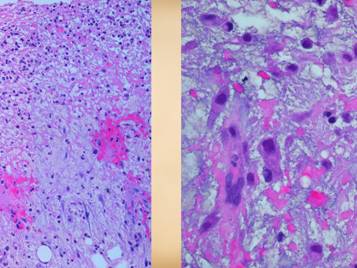

21

When hypercoagulable patients present with chronic ulcers, some of their histories can be otherwise quite benign.  The wounds and their treatment can be slow, subtle, persistent, recurring, frustrating, refractory, but a patient’s general health and well-being are not in any immediate jeopardy – or are they?  Some such patients have histories of serious prior events, such as blindness due to retinal artery occlusion, strokes, limb loss from trauma, recurrent pulmonary “emboli”, and other macro-vascular events.  All hypercoagulable patients have these potential risks.  With the appropriate trigger or generalized inflammatory or hyper-thrombotic state, even the micro-vascular events can become extensive and life-threatening.  This slide shows three patients who died from these conditions.  Left upper:  this patient had heart surgery, and a week or two after starting warfarin, he developed multiple non-embolic skin and extremity infarcts.  Peripheral arteries were normal.  Lab studies confirmed low APC resistance and probable factor V abnormality.  The events were non-survivable.  Lower:  this patient had sigmoid resection for a diverticular colo-vesical fistula.  Bowel necrosis resulted in progressive enterectomy, and with each procedure, more of the abdominal wall died.  This view shows a necrotic ileostomy and abdominal fascia infarcts.  Lab studies confirmed APC deficiency.  Histology confirmed diffuse primary micro-thrombosis (i.e. not post-mortem changes, and absence of significant inflammation pins the thrombosis as the primary event).  The events were non-survivable.  Right upper:  This patient had refractory leg ulcers with active progressive infarcts during the period of observation.  Lab evaluation confirmed primary low proteins C & S.  She died from a stroke shortly after making the diagnosis and planning treatment.  These are non-trivial diagnoses, and their management must include comprehensive and long term planning including the role of anti-coagulation.